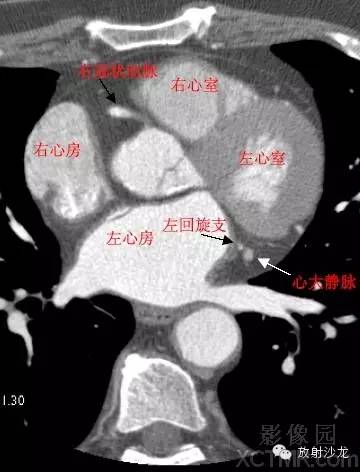

心脏冠状动脉CT解剖中文详细标注

LA -Left Atrium左心房

RA -Right Atrium右心房

LV -Left Ventricle左心室

RV -Right Ventricle右心室

LCX -Left Circumflex Artery左回旋支

RCA -Right Coronary Artery 右冠状动脉

GCV–Great Cardiac Vein心大静脉